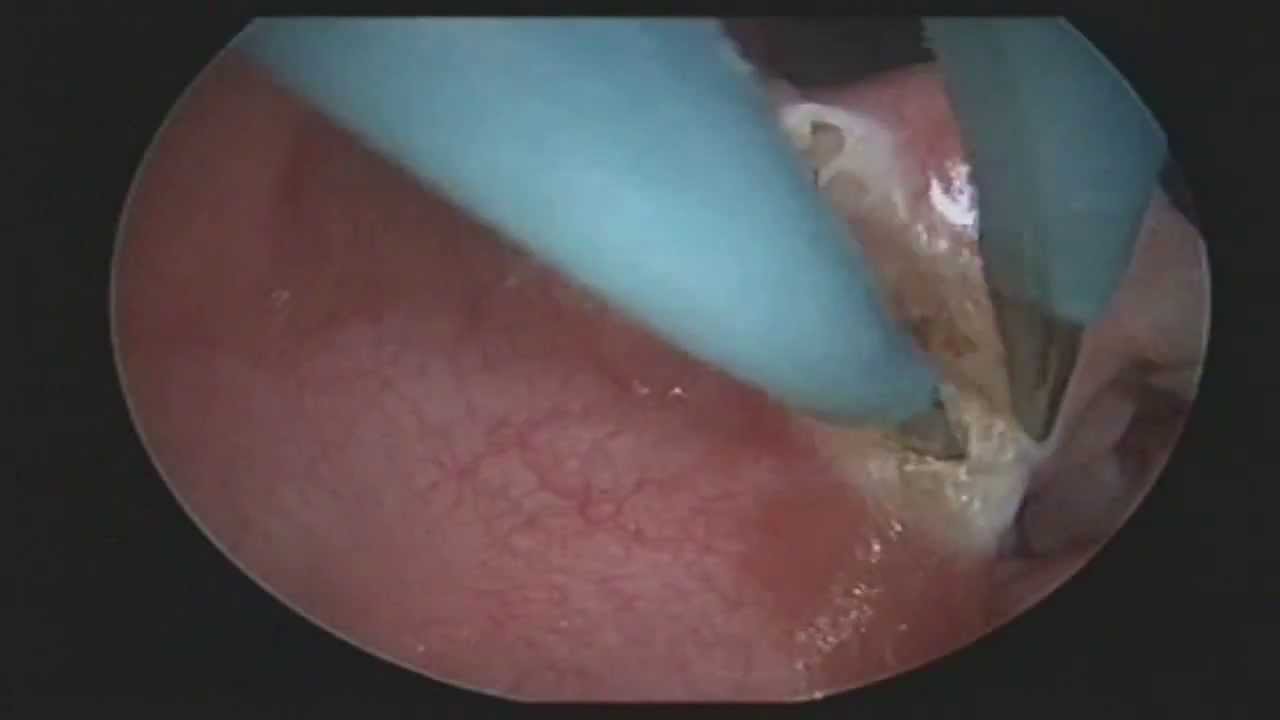

Fiberoskopia Warszawa inaczej badanie fiberoskopowe (endoskopia nosogardła) jest jedyną metodą weryfikacji, czy mamy do czynienia z przerostem trzeciego migdałka. Warto bowiem pamiętać, że w przeciwieństwie do migdałków podniebiennych, które możemy zobaczyć po szerokim otwarciu ust, trzeciego migdałka nie da się zobaczyć. BADANIE ENDOSKOPOWE W CENIE KONSULTACJI WARSZAWA OTOLARYNGOLODZY24

• Nasofiberoskopia

Ta Pani Doktor oprócz empatii ma niezwykłą wiedzę leczenia i operowania zatok. Badanie zatok odbywa się często za pomocą dziennika z kamerą a nie wywiadu dotyczacegobdolwgliwisci.Jest trochę genialna